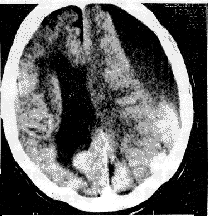

1.CT MRI檢查 腦室系統擴大並尤以側腦室前角為著;側腦室周圍特別是額角部有明顯的間質性水腫帶;腦室擴大的程度甚於腦池的擴大;腦回無萎縮表現 腦溝不加寬。不過,需要與腦萎縮相鑑別,因為嚴重腦挫傷、軸突損傷、腦缺血 缺氧和壞死等造成的腦萎縮也具有腦室擴大的CT影像。後者的特點是:側腦室普遍擴大 腦溝增寬、無腦室周圍的透亮水腫區。MRI檢查雖與CT所見相同,但更為明確和清晰:首先是側腦室前角的擴張及腦室周圍的間質性水腫帶,可於T2加權圖像上顯示出明顯的高信號;其次於冠狀面可以測出兩側室頂之間的夾角小於120°,相反在腦萎縮病人此角則常大於140°;再者於矢狀面尚可看到第三腦室呈球形擴大,視隱窩和漏斗隱窩變淺變鈍,而在腦萎縮病人,其第三腦室前後壁、漏斗隱窩、視隱窩則無明顯變形,雖有擴大但仍保持其原有輪廓。